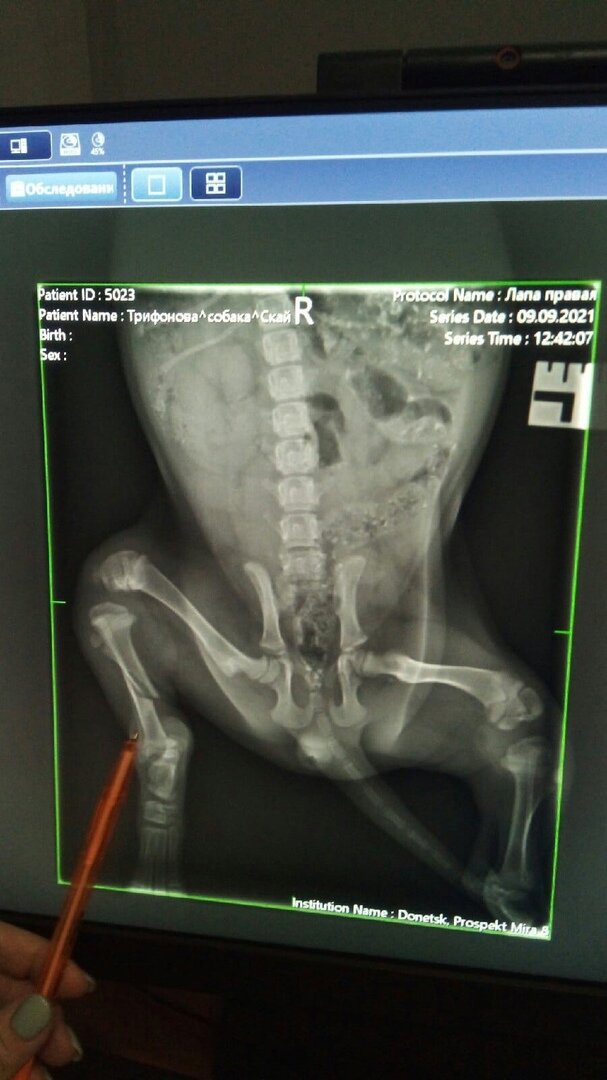

Щенок Скай: девочка очень резвилась во время прогулки

Наша СКАЙ сломала лапку…. (малышка так резвилась во время прогулки). Щенок Скай: очень позитивная и энергичная девочка Девочка - бездомная… и вот такая неприятность… Курирует ее по прежнему волонтер Алла Юрченко. Щенок Скай и котенок Рыська - это просто незабываемый дуэт хвостатых актеров Ей так одиноко… 🥺Она теперь сидит на стационаре волонтеров. Еще она ждет, когда ее смогут проведать и привезут вкусняшки. Скай в стационаре ветклиники ЦВМ. Сделали рентген и сегодня будет операция….НО по стационару огромный долг 😞 Помогите пожалуйста - нужна помощь🙏🏻 И конечно же счастливый билетик по восстановлению.

Скай в стационаре ветклиники ЦВМ. Сделали рентген и сегодня будет операция….НО по стационару огромный долг 😞